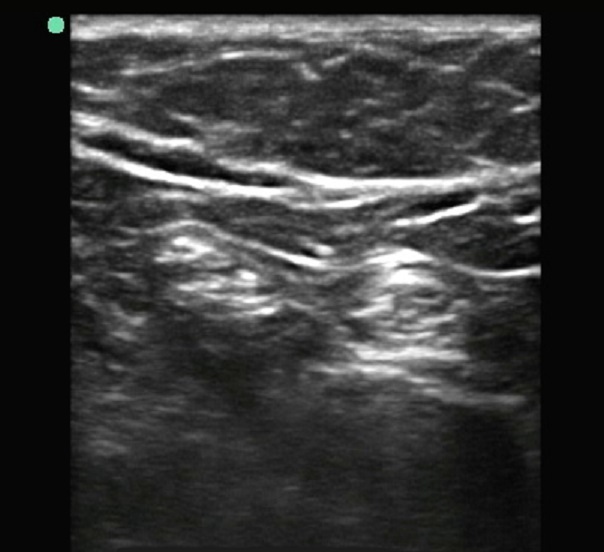

膝窩神経分岐部画像